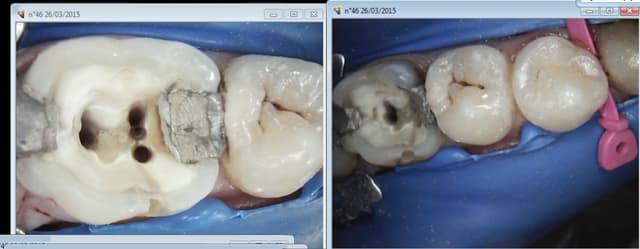

Endo 45 47. Aucun problème, aussi rapide à poser qu'une dent isolée. Cerise sur le gateau la tronculaire était un peu faible ( pulpite sur 47) un coup de quick sleeper sans déposer la digue et roule ma poule.-))))))

Conclusion: meilleur compromis pour moi split dam avec digue rigide, étanchéité plus que satisfaisante.